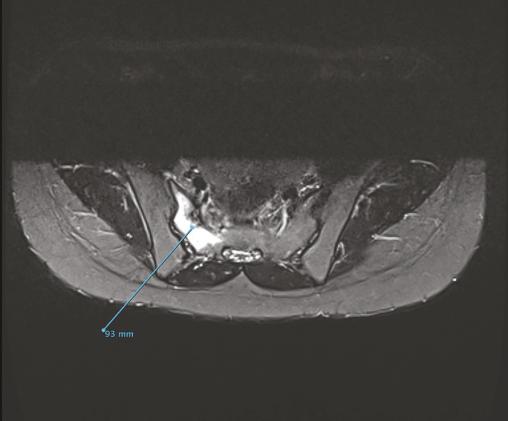

Engagée depuis 2 mois, cette jeune militaire consultait pour des paresthésies des orteils, sans notion de traumatisme aigu. Sédentaire auparavant, elle n’avait aucun antécédent particulier. Son indice de masse corporelle était de 20 kg/m2. L’examen notait une douleur neurogène avec trouble des sensibilités prédominant à l’extrémité du pied droit, sans syndrome radiculaire ni rachidien, d’horaire non mécanique. Le test de Faber était positif. Réalisée en seconde intention, l’IRM du bassin (v. figures) montrait une fracture de contrainte de l’aileron sacré droit. Le bilan biologique était sans particularité. Une cure courte d’anti-inflammatoires non stéroïdiens et la limitation au minimum des activités physiques entraînaient la guérison en 8 semaines.

La fracture de fatigue du pelvis est liée à un déséquilibre de l’homéostasie osseuse dans un contexte d’hypersollicitation. Elle est connue et sous-diagnostiquée chez les coureurs de fond (1 à 7 % de ces lésions), et les « nouveaux » sportifs notamment les jeunes recrues militaires.1 Le tableau clinique est non caractéristique et non spécifique. La radiographie standard ne permet pas de poser le diagnostic. L’anamnèse (changement, rythme, sport), le terrain et les signes négatifs orientent pour infirmer les diagnostics différentiels (discopathie, canal lombaire étroit, lésion cancéreuse).2 Six semaines de repos suffisent, en règle générale, pour guérir et reprendre progressivement le sport en charge. Toute femme ayant eu une fracture de stress doit bénéficier d’une exploration à la recherche du syndrome « triade de l’athlète féminine »(aménorrhée, trouble alimentaire et ostéoporose).